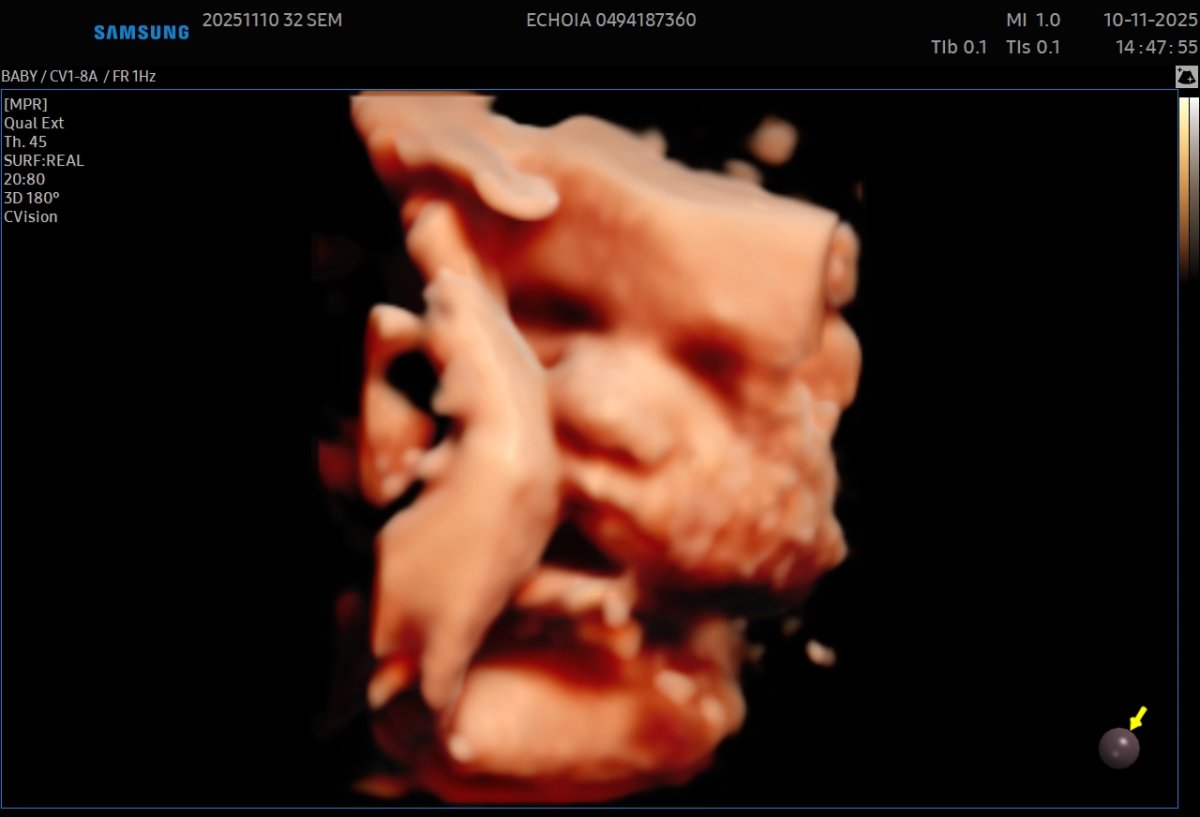

Gallerie de photos